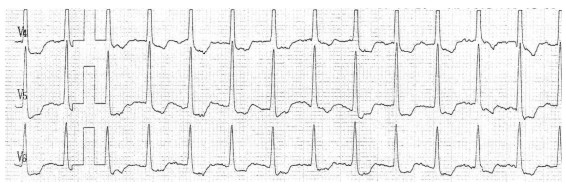

ECG basal: ritmo sinusal de 90 cpm, P y PR normales. Eje eléctrico próximo a 0º. Bloqueo incompleto de rama derecha. Rotación antihoraria del ventrículo izquierdo.

Figura 1. ECG basal